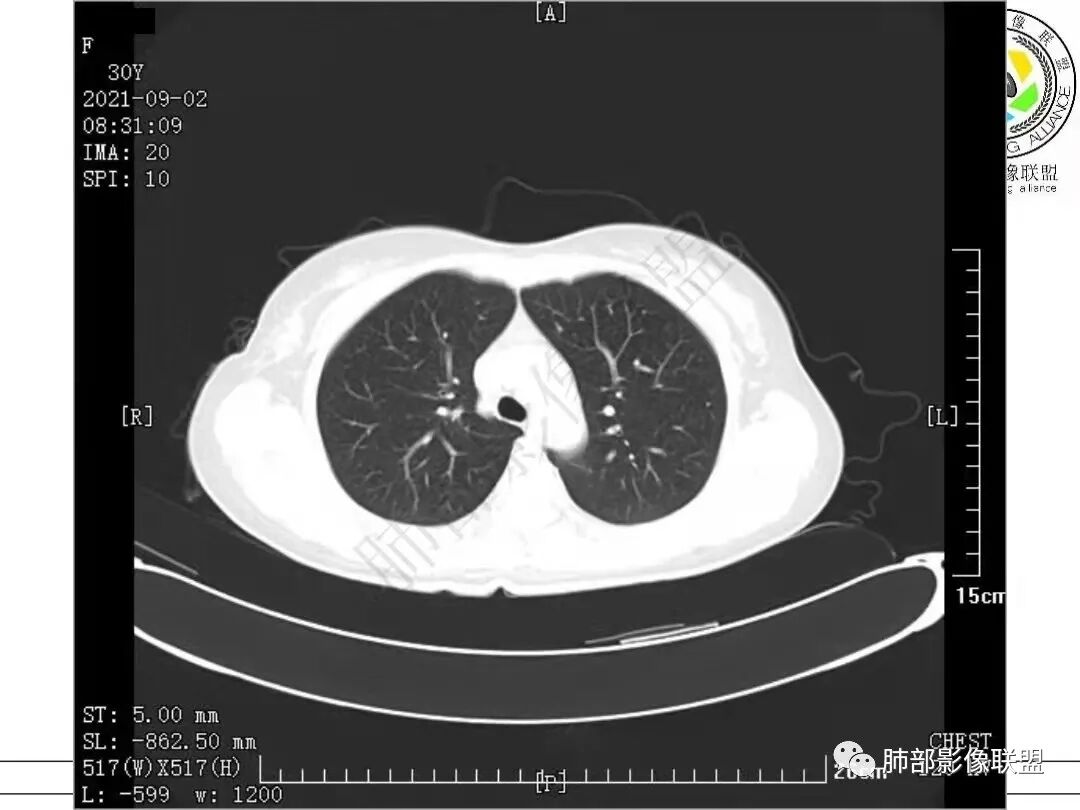

1.病例一:68岁男性,体检发现肺结节,肿瘤标志物CA199、CA50、CEA升高,其中CEA升高显著,超过正常范围的5倍以上。右肺下叶胸膜下结节影,整体较膨隆,部分层面可见锯齿状边缘,边界清晰,周围可见细毛细影,可见血管集束征、胸膜牵拉。密度不均,可见磨玻璃密度区及空泡征,胸膜下脂肪间隙显示不清。增强后显示轻、中度强化。